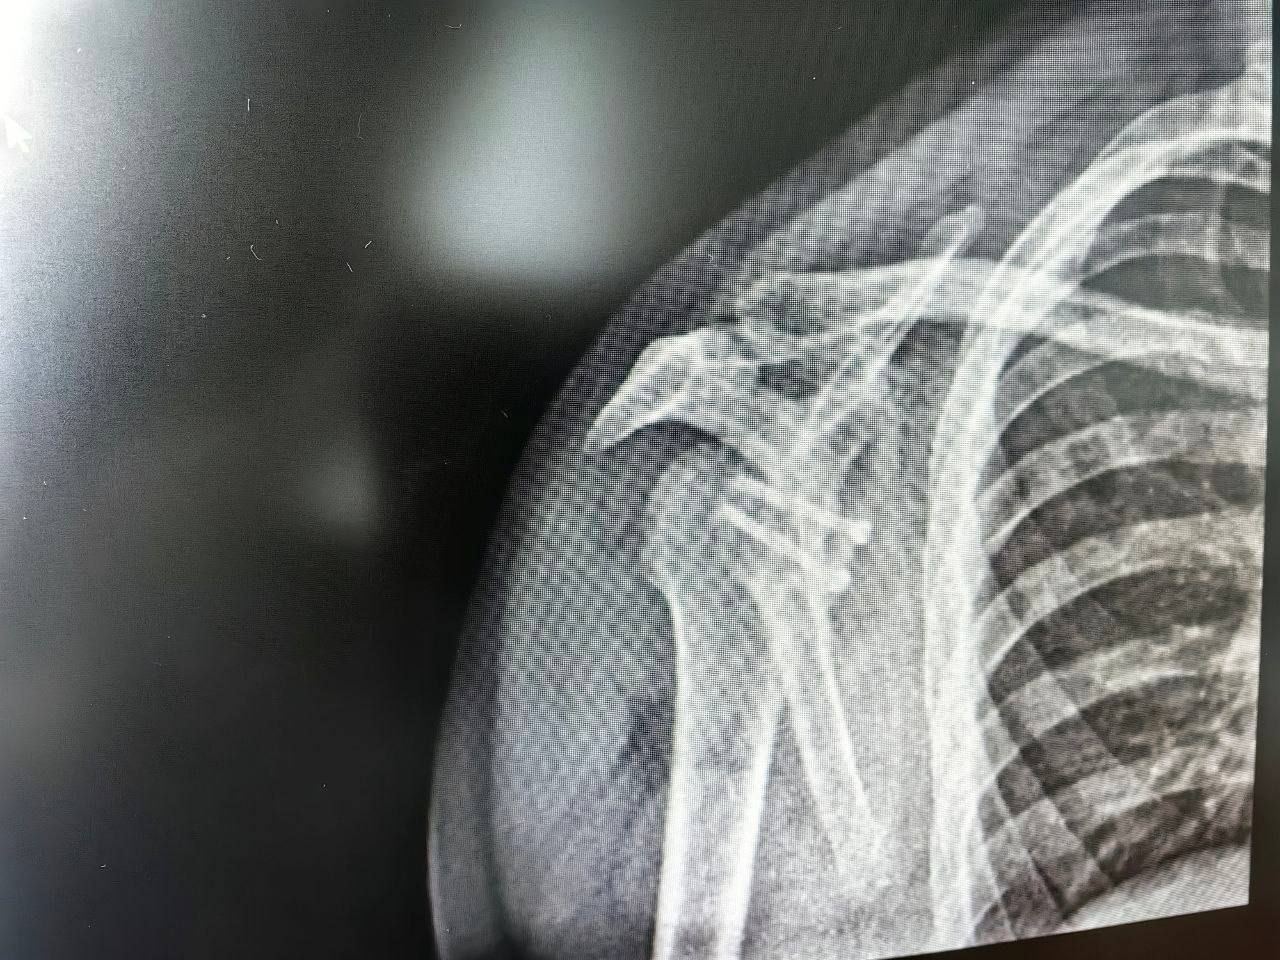

Столкнувшиеся с такой же проблемой друзья по команде уже перенесли операции. Кто-то ездил для этого в Москву, а кто-то - за границу. Данила решил довериться сургутским травматологам-ортопедам. Врачи диагностировали давний разрыв суставной губы и обширный дефект кости. Чтобы стабилизировать сустав, им необходимо было восполнить утраченную костную ткань.

Как раз в этом и заключается суть операции Латарже. Для замещения дефекта используют фрагмент клювовидного отростка лопатки. Вместе с сухожилием его перемещают туда, где образовался костный дефицит, и фиксируют специальными винтами. За счёт транспозиции костного блока появляется дополнительная площадь контакта головки плеча с лопаткой, укрепляется суставной край. Усиливает этот эффект и перенесённое сухожилие. Образовавшаяся сухожильная петля будет препятствовать смещению головки плечевой кости.